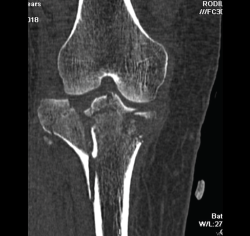

1. Fracturas

Es esencialmente útil en la valoración de los trazos de fractura, de su extensión, del escalón intraarticular y el desplazamiento. También es importante en la planificación del tratamiento de las fracturas intraarticulares complejas.

Los nuevos equipos, con múltiples detectores, permiten realizar cortes finos (submilimétricos) y reconstrucciones en cualquier plano del espacio o tridimensionales (3D) de gran calidad, que facilitan la valoración de estas lesiones(7).

1.2. Tibia (Figura 20)

Figura 20. Corte de reconstrucción coronal de tomografía axial computarizada de rodilla: fractura de ambas mesetas tibiales.